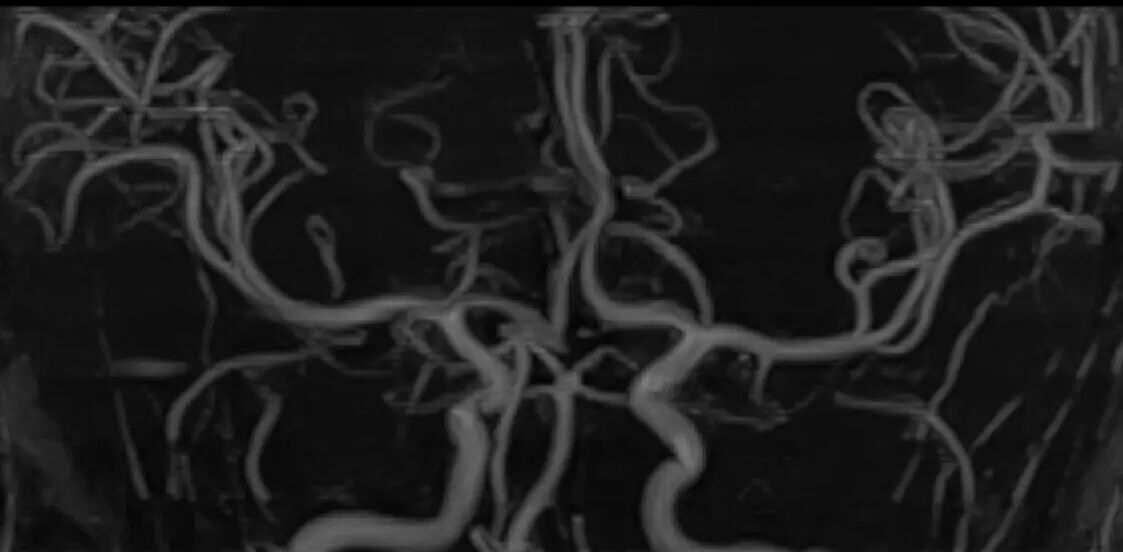

头部MRA成像

·2分钟颅脑MRA扫描方案(2分15秒);